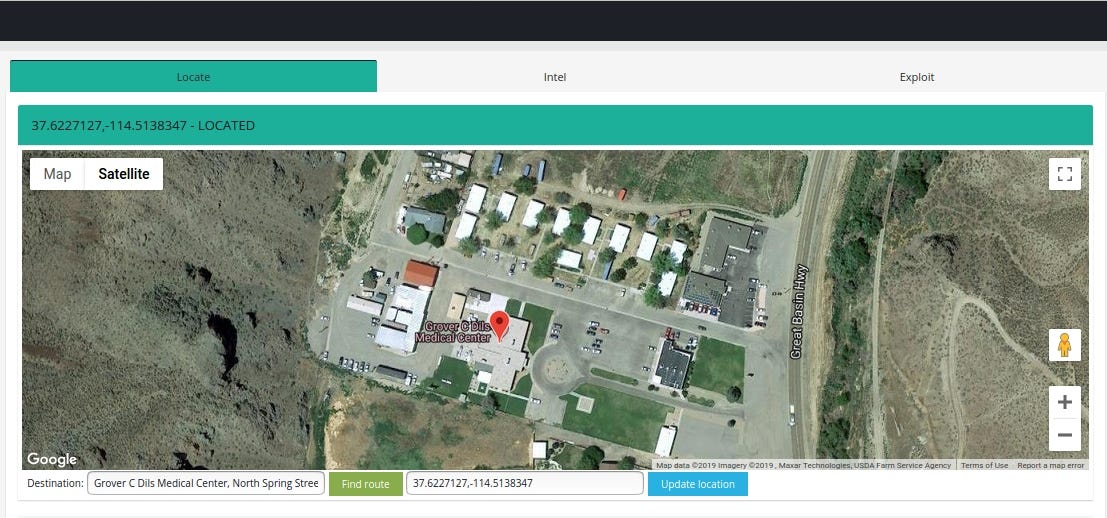

Case #1 Grover C. Dils Medical Center, Caliente, Nevada, United States

Medweb’s web based RIS/PACS offers improved scheduling and workflow solutions including online eligibility-confirmation tools to enable faster patient registration and revenue reimbursement.

Query: “html:’DBA Medweb. All rights reserved.’”

Facility name is exposed in HTML title and content

It’s worth to notice that SSL certificate is issued to Common Name: Development and Organization: Medweb

Geolocation is quite easy in this case, IP based location points to the nearest city but with ꓘamerka you can draw a route to the Medical Center